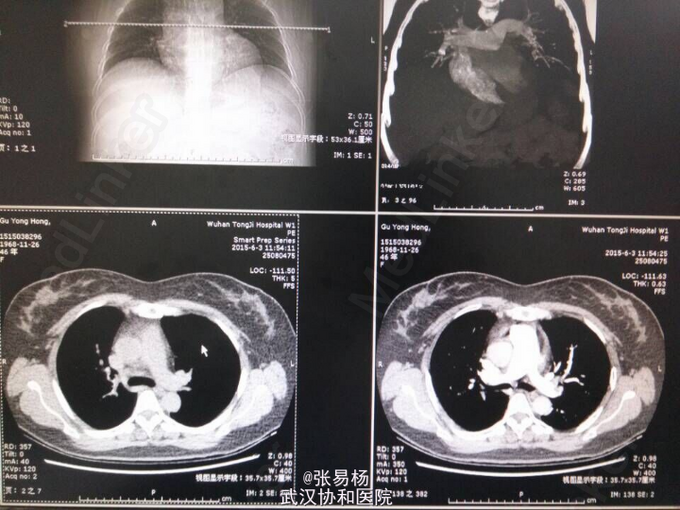

患者,女,47岁 主诉:双下肢胀痛不适10余天 现病史:患者于10余天前无明显诱因出现双下肢肿胀,有轻微压痛,久站及行走后加重,平卧后缓解,余无特殊症状。3天前门诊行双下肢彩超示:双侧小腿肌间静脉血栓形成。 既往有高血压病史3年余,口服利血平片,血压控制可余无特殊。

查体:双下肢水肿,指压征阳性,余无特殊。 辅检:肺动脉血管成像,CT-三维成像示:左肺动脉及其分支,右肺上叶肺动脉及其分支,右肺下叶后段肺动脉充盈缺损,考虑栓塞双肺血管纹理增强,考虑灌注不足所致。